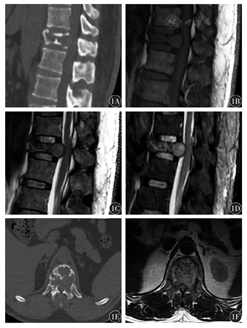

(1)5例椎体病灶:椎体均压缩变扁,呈溶骨型骨质破坏,并可见软组织肿块,其中1例呈膨胀型改变,1例呈虫噬样改变,2例呈"微脑征"(图1)。CT病灶呈软组织密度,残存骨嵴呈线样高密度。MRI T1WI呈等/低信号,T2WI呈低/稍高信号,残存骨嵴呈低信号。增强扫描后病灶明显均匀强化。2例病灶边界模糊,3例病灶边界清,部分病灶向后侵及椎体附件、延伸至椎管,椎管狭窄。(2)2例颅骨病灶:病灶直径均>5 cm,呈穿凿样骨质破坏,向颅板内外膨胀性生长,呈双凸状。CT均呈稍高密度。MRI的T1WI均呈等信号,T2WI 1例呈等信号,1例呈混杂低信号。1例增强扫描呈明显均匀强化。(3)1例肋骨病灶:病灶呈溶骨型骨质破坏,CT呈等密度,T1WI呈低信号,T2WI呈稍高信号(表1)。

脊柱SBP以胸椎最常见,其次为腰椎、颈椎和骶骨。病灶多累及脊椎前柱,主要表现为椎体内不同程度的溶骨型骨质破坏,呈虫噬样、穿凿样,伴有椎体压缩,可同时累及椎弓、椎板、椎体两侧软组织及椎管结构。"微脑征"为椎体SBP的特异性征象[6],是椎体受累后残存骨小梁在应力作用下代偿性增生所致。CT表现为骨破坏边缘的皮质增厚,病灶内可见高密度残存骨嵴,MRI呈曲线样低信号穿梭于等/高信号肿瘤组织中,类似于缩小版的大脑半球脑沟、脑回影[7]。本组中2例具有此典型征象,影像医师做出了正确诊断。SBP因血供丰富,增强扫描时多呈明显均匀强化。